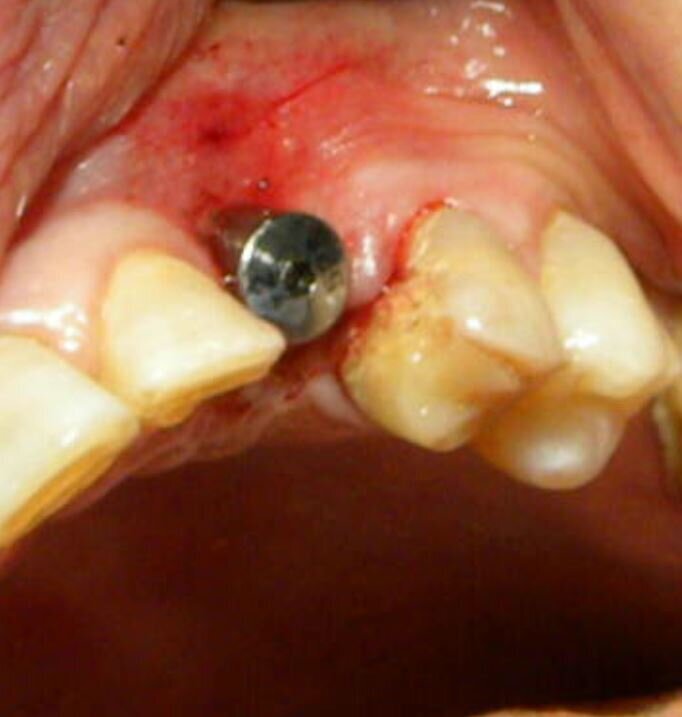

Fig. 10 - Caso clinico 3. Scopertura implantare: è possibile eseguire una precisa opercolectomia.

Fig. 11 - Caso clinico 3. Posizionamento della vite di guarigione.